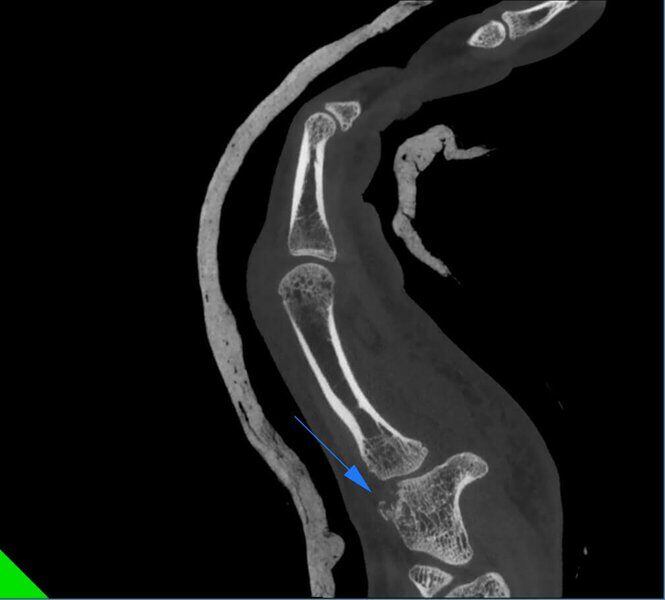

Fractura de la cabeza del radio en paciente con yeso.